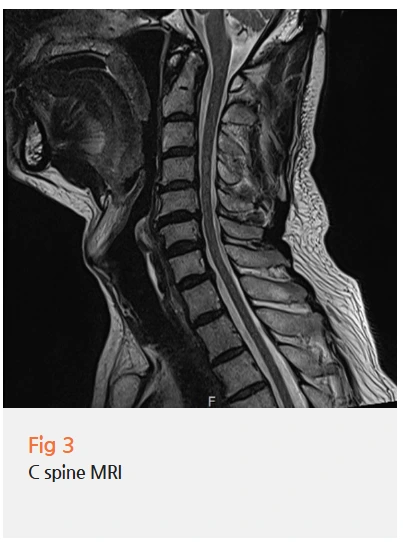

저는 환자분께 먼저 당일 뇌 MRI와 MRA 검사를 권했어요.

얼굴 감각이상과 귀 통증이 함께 나타나는 경우,

뇌신경 병변 가능성을 먼저 확인해야 하거든요.

검사 결과, 다행히 뇌에는 아무런 문제가 없었어요.

%EA%B7%B8%EB%A6%BC2.png?type=w966

✔️ 뇌 MRI, MRA (뇌혈관 검사)

특히 중요한 건 뇌와 목을 함께 봐야 한다는 거예요.

귀 통증의 원인이 뇌신경 병변일 수도 있고,

목에서 나오는 말초신경 문제일 수도 있거든요.

그래서 저는 두 부위를 모두 꼼꼼히 확인해요.